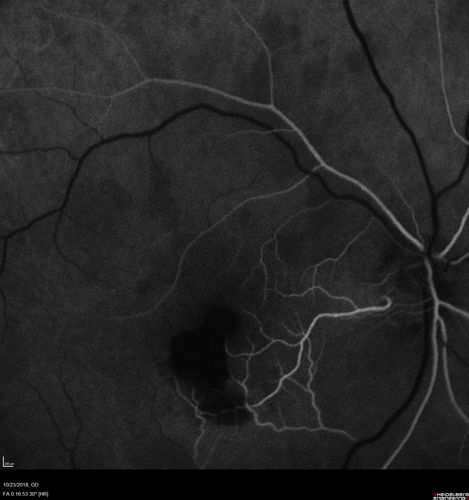

Valsalva Retinopathy - Macular Hemorrhage - Permanent Vision loss - Intraretinal Blood

65 year old man with sudden vision loss in the right eye. Initial vision 20/200. VA improved to 20/50 in one year. Had carotid stenosis